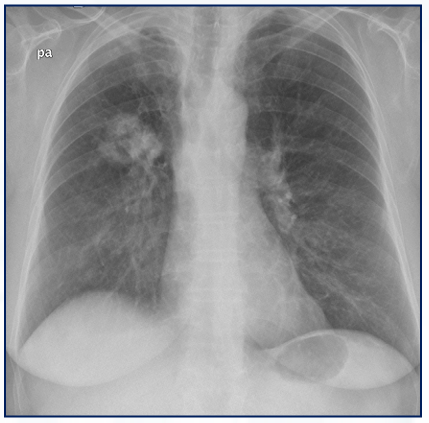

Qual o achado desse Rx de tórax PA e perfil?

Hiperinsuflação pulmonar, frequente na DPOC.

• Aumento do diâmetro AP do tórax

• Retificação das cúpulas diafragmáticas

• Aumento do espaço retroesternal

• Aumento do espaço intercostal

• > 10 costelas posteriores

• Pulmões hipertransparentes

• Horizontalização das costelas

• Coração em “gota